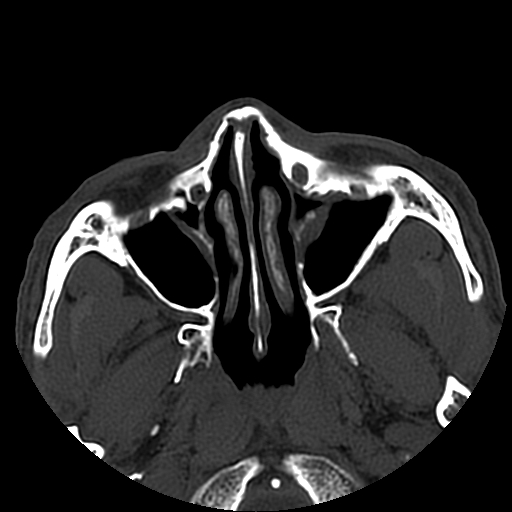

以下是引用liaoqiang在2008-7-16 21:15:00的发言:[br]右侧鼻骨骨折

以下是引用zxd95在2008-7-16 21:39:00的发言:[br]右侧上颌骨额突骨折。[br][br][br][br]